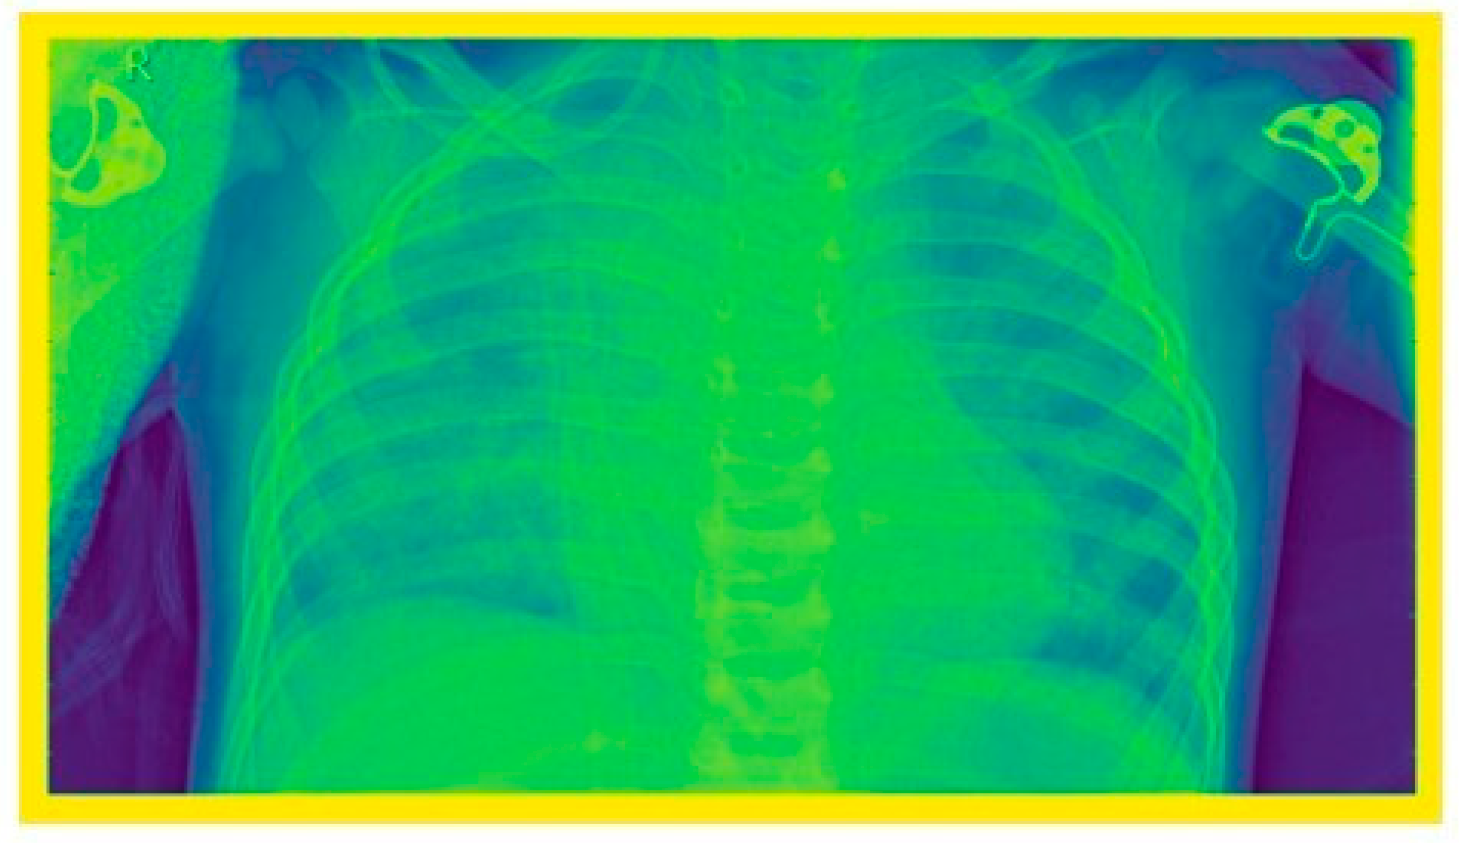

2.4. Image Enhancement Techniques